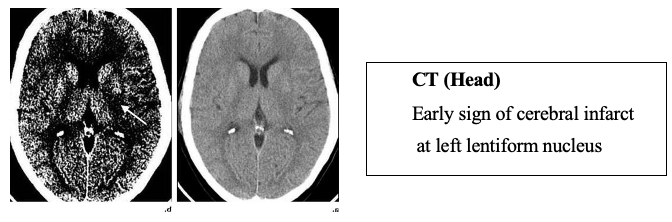

A 54 year old right handed lady presented with sudden onset of right hemiparesis and slurred speech 1 hour ago. She did not have any medical checkup previously. On examination, GCS was 15/15, right facial palsy (UMN), slurred speech, right hemiparesis (power 3/5), up going planter response on right side. NIHSS score was 12. Blood pressure was 180/110 mmHg, pulse was 84/min, heart and lungs were unremarkable. Complete blood picture, urea and electrolytes, creatinine and coagulation profiles were normal.

- ECG and CXR – Normal

Question: How would you manage her blood pressure?

Discussion: To treat or not to treat high BP in acute ischaemic stroke has been debated for more than 30 years ago and there was no definitive answer till 2018. Based on dysfunctional cerebral auto-regulation during acute stroke, there is concern about lowering BP due to: